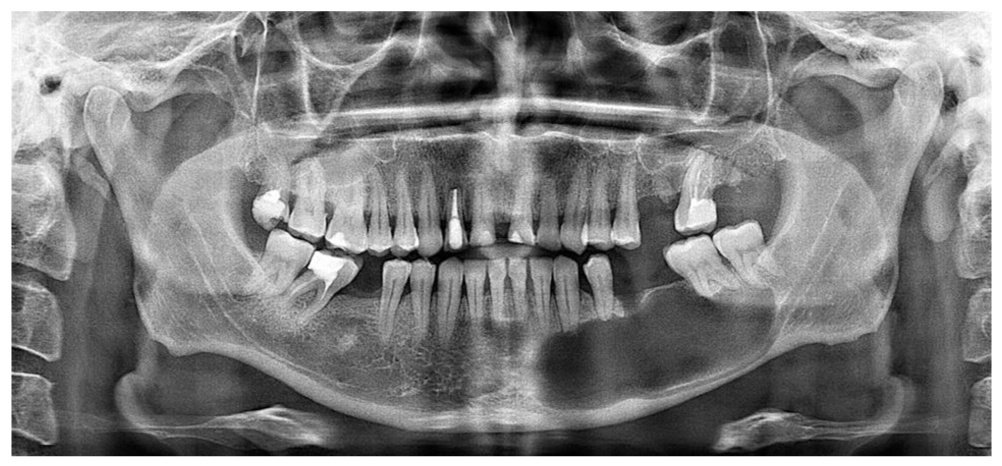

Контрольная компьютерная томограмма через 2 мес после завершения лечения пациента демонстрирует полное замещение кистозной полости вновь образованной костной тканью (рис. 5).

Рис. 5. Ортопантомограмма пациента И. перед началом стоматологической реабилитации по поводу частичной утраты зубов. / Fig. 5. Orthopantomogram of patient I. before the start of dental rehabilitation for partial loss of teeth.

В дальнейшем пациенту планируется комплексная стоматологическая реабилитация с восстановлением высоты прикуса и протезированием с использованием дентальных имплантатов. Хирургический этап установки искусственных внутрикостных опор с целью оценки качества проведенного лечения объемного полостного образования нижней челюсти с диструктирующим ростом представлен на рис. 6.